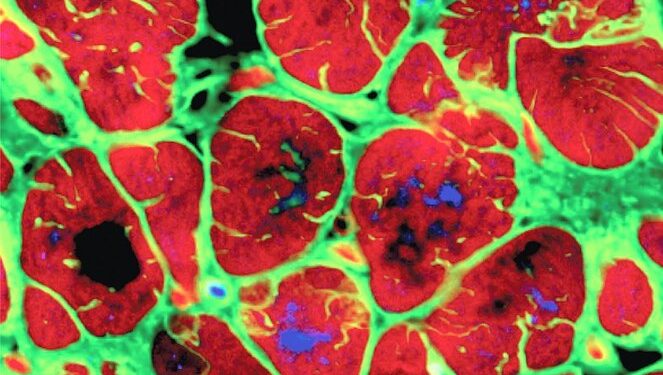

Studimi u përqendrua në gjenin CCNA2, i cili ka një rol thelbësor në ndarjen qelizore gjatë zhvillimit në mitër, por ndalon së funksionuari pas lindjes. Studiuesit synuan ta riaktivizojnë këtë gjen për të verifikuar nëse ai mund të ndihmojë në gjenerimin e qelizave të reja që do të zëvendësonin ato të dëmtuara pas një ataku kardiak ose pamjaftueshmërie kardiake. Pjesa eksperimentale përfshinte inokulimin e gjenit aktiv në qelizat e muskulit kardiak të kultivuara in vitro, ku u vëzhgua replikimi i tyre.